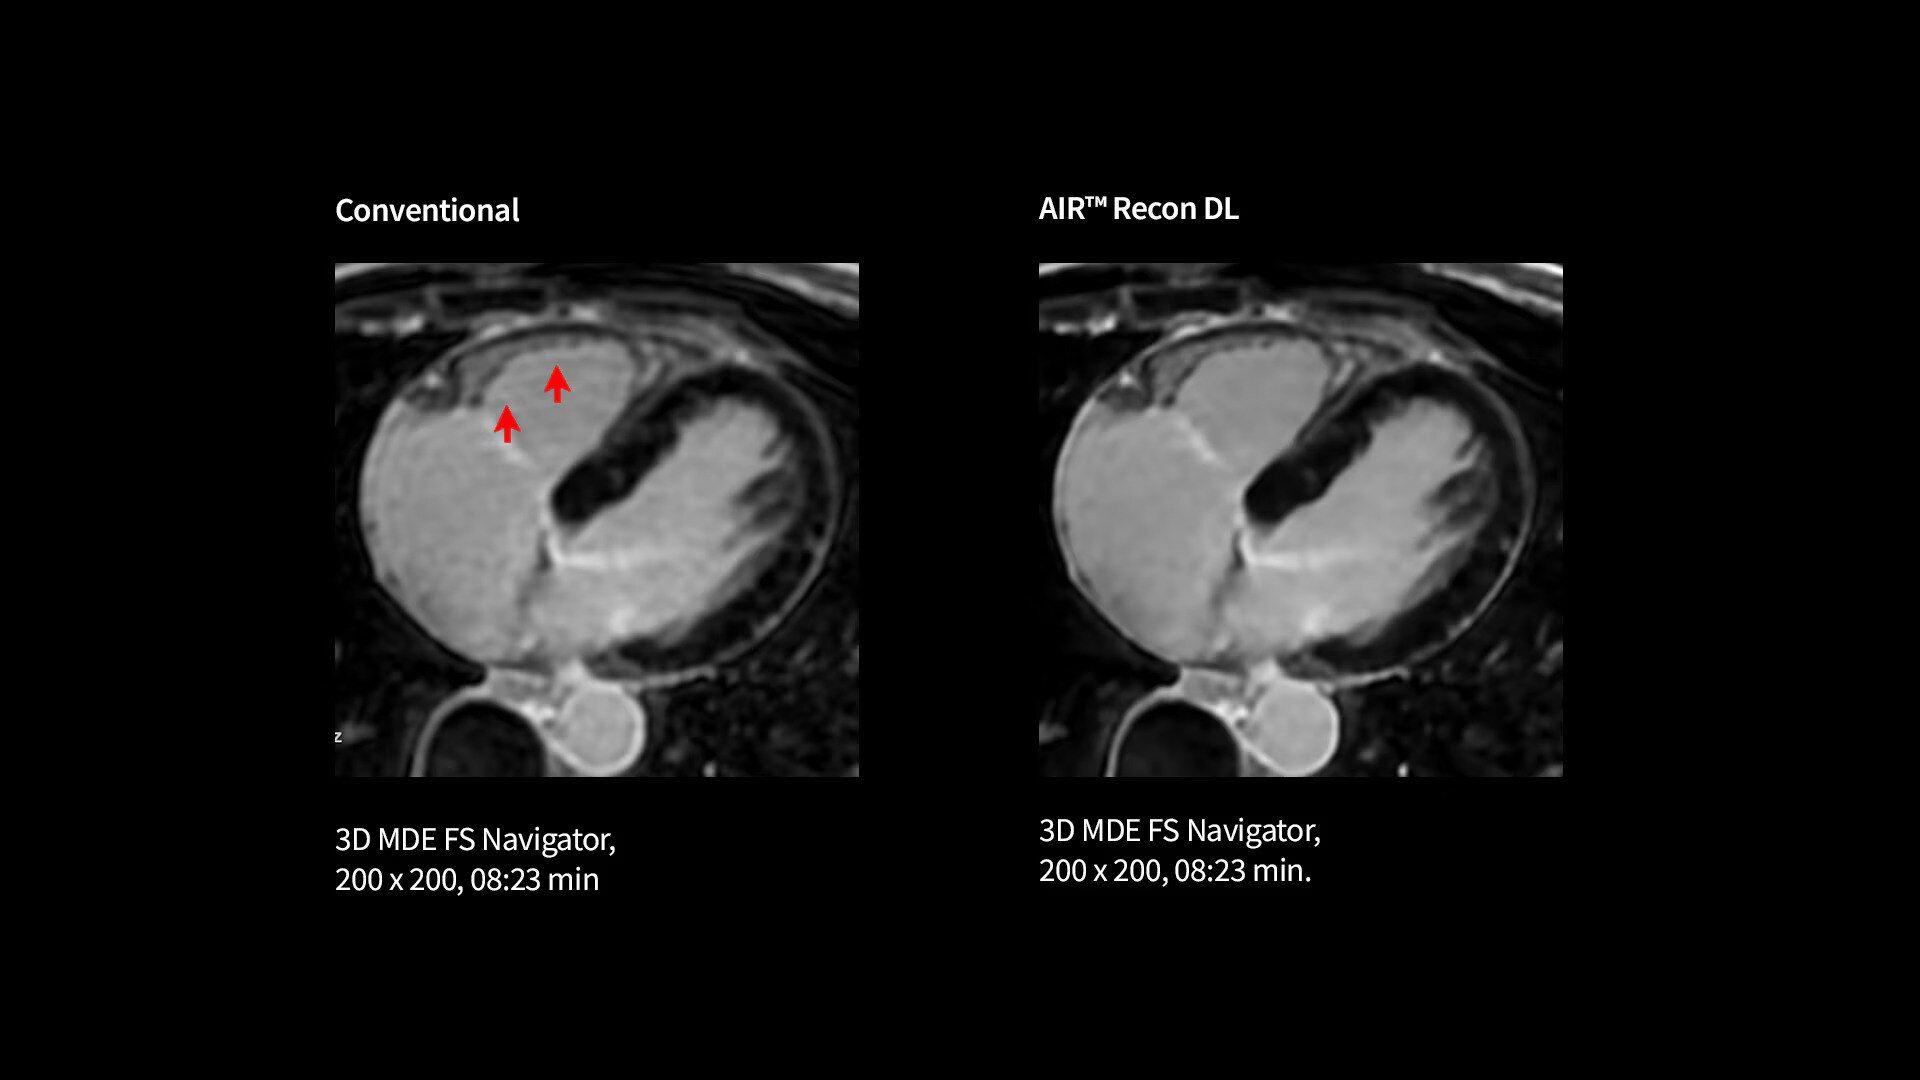

Every step of our cardiac MR assessment is compatible with our pioneering deep-learning algorithms, including: morphology, function, perfusion, mapping and myocardial viability with

late enhancement.

Your teams can capture clarity with AIR™ Recon DL, a revolutionary technique to boost image quality, providing accurate anatomic information and advanced soft tissue contrast. It’s already transformed the lives of millions of patients worldwide since 2021. Thanks to Sonic DL™ they can also now assess cardiac viability faster than ever before, with as little as 15 to 20 minutes per scan.*†